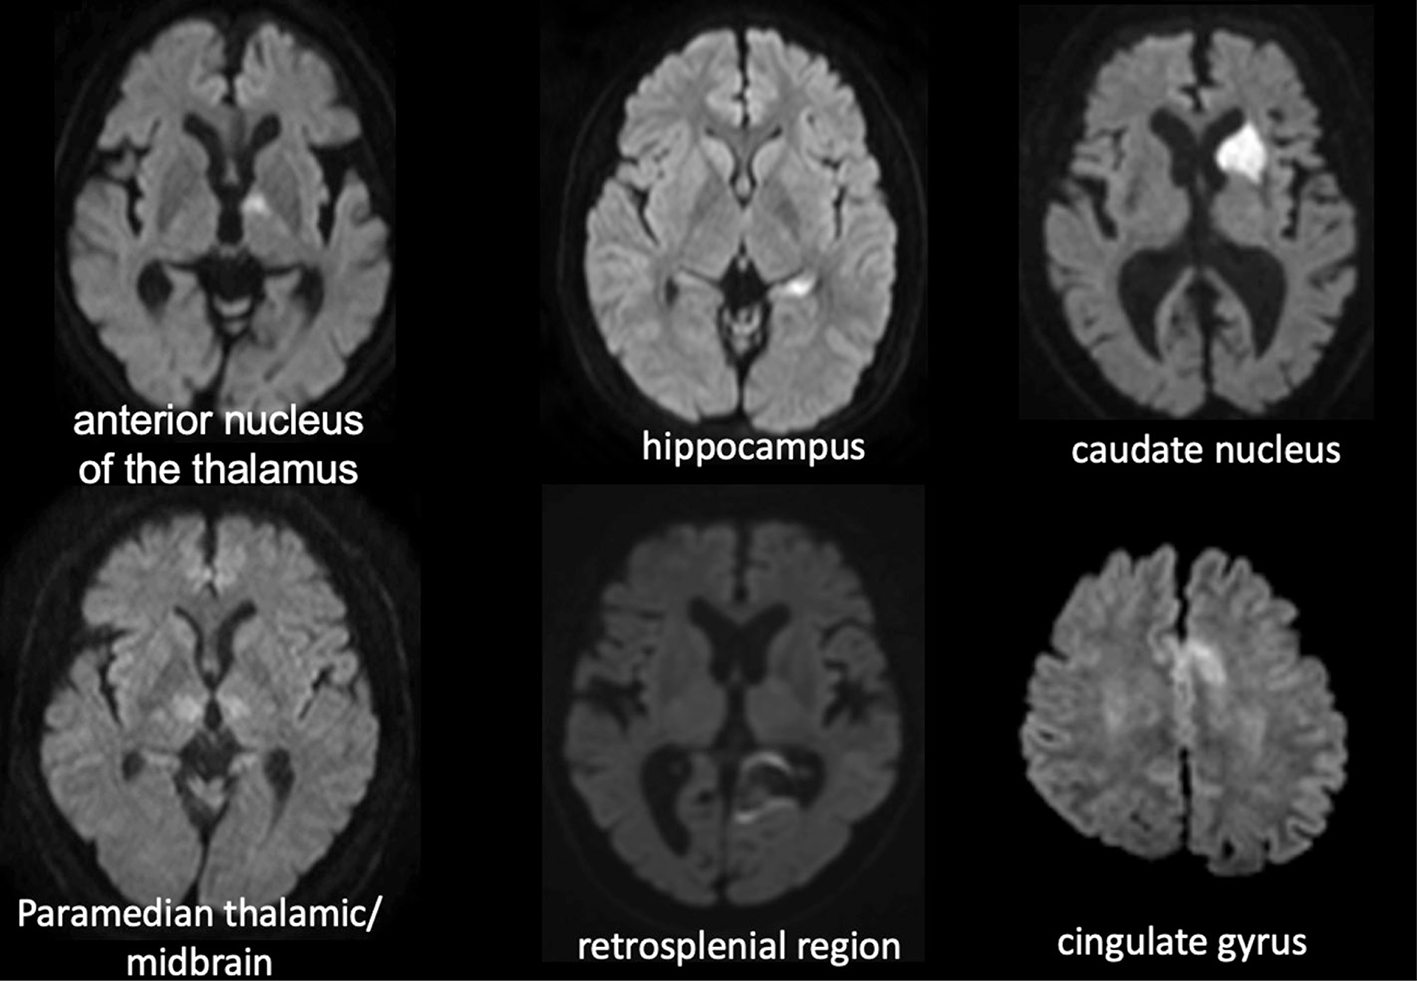

Fig 4

Figure 4. Lesions in patients with episodic memory impairment. Memory impairment occurs when strokes occur in areas associated with episodic memory, including the hippocampus, anterior thalamic nucleus, medial papillary nucleus, parahyppocampal gyrus, amygdala, medial thalamic nucleus, and orbitofrontal cortex.

The neural circuits related to episodic memory include the Papez circuit (medial limbic circuit) centred around the hippocampus, anterior thalamic nucleus, medial mammillary nucleus, and parahippocampal gyri, as well as the Yakovlev circuit (ventrolateral limbic circuit), centred on the amygdala, medial thalamic nucleus and orbitofrontal cortex. Although each circuit is independent of the other (6), they are very closely related (Figure 3), and cerebral haemorrhage or cerebral infarction at these sites manifests as memory loss (Figure 4).

The manifestation of memory loss associated with medial temporal lobe lesions is variable. The hippocampus does not store or retrieve memory; instead, it plays an important role in encoding memory and is involved in consolidating memories formed within the recent past (7). Damage localized to the hippocampus presents as anterograde amnesia, but is not always associated with retrograde amnesia, and old memories are often retained (8). Widespread damage to the medial aspect of the temporal lobe, such as the hippocampus and parahippocampal gyrus, impairs retrieval of old memories and results in severe backward amnesia (9).

The posterior cingulate gyrus has fibrous connections with the anterior cingulate gyrus, medial aspect of the temporal lobe, prefrontal cortex, posterior parietal lobe, thalamus, and caudate nucleus. Even lesions in the retrosplenial region present with memory loss, known as retrosplenial amnesia, which is thought to be caused by impairment of the fibrous communication of the memory circuit between the hippocampus and the anterior nucleus of thalamus due to damage to the posterior cingulate gyrus (10). It reportedly occurs more frequently as a sequela of hemorrhage than that of infarction (11, 12).

The thalamus receives vascular supply from the anterior and posterior circulation (13). The thalamotuberal arteries (polar artery) that branch from the posterior communicating artery perfuse the anterior nucleus of thalamus, and damage to this area presents as episodic memory loss. The paramedian thalamic artery, which originates from the posterior cerebral artery, traverses the dorsomedial nucleus of thalamus, and may also branch bilaterally from the posterior cerebral artery on one side (14). Lesions of the bilateral dorsomedial nucleus of the thalamus can result in severe impairment of consciousness. Damage to these areas of the thalamus due to cerebral infarction, surgical invasion (15), and/or cerebral hemorrhage (16) causes memory loss (Figure 5).